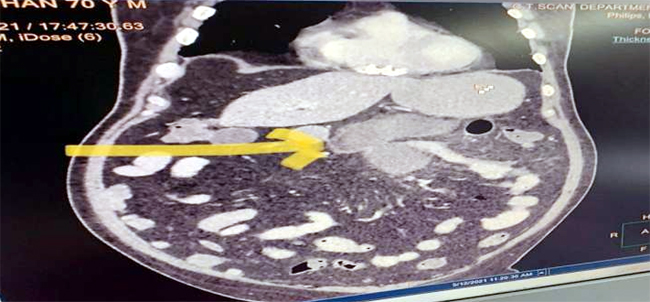

लेकिन सीटी स्कैन के बाद डॉक्टरों ने इस मरीज में छोटी आंत में म्यूकरमाइकोसिस का पता लगाया. डॉक्टरों ने बिना समय बर्बाद किए ऑपरेशन करने का फैसला किया क्योंकि सीटी स्कैन से पता चला कि उसकी छोटी आंत में छेद हो गया था.

जबकि 68 वर्षीय दूसरे मरीज के मामले में डॉक्टरों का कहना है कि उन्होंने भी कोविड -19 से ठीक होने के बाद पेट में हल्के दर्द का अनुभव किया. मरीज शुगर से पीड़ित हैं और उन्हें इलाज के दौरान उन्हें स्टेरॉयड दिया गया. इनके सीटी स्कैन के छोटी आंत में एक छिद्र होने का पता चला, जैसा कि पहले मरीज में था.